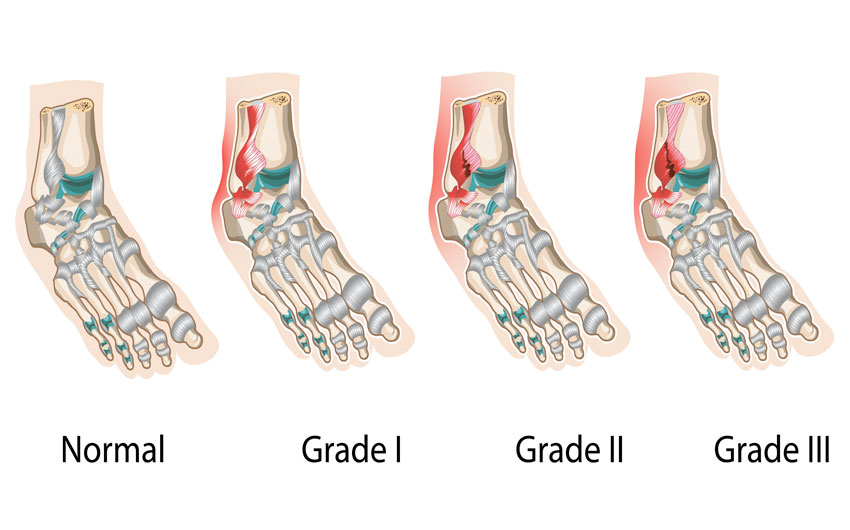

Разрывы, относящихся к голеностопу связок, делятся на три вида:

- частичный разрыв. Травмируются отдельные волокна, нередко травму называют растяжением, но это некорректное обозначение, так как связки повышенной эластичностью не наделены;

- надрыв. Характеризуется микроразрывами большей части волокон голеностопных связок, но функцию поддержки они продолжают обеспечивать;

- полный разрыв. Самая серьезная по тяжести травма, чаще всего сопровождается отрывом связок от физиологического места крепления.

Классификация разрывов необходима для выбора верной тактики ведения больного и прогноза срока восстановления функциональности сустава.